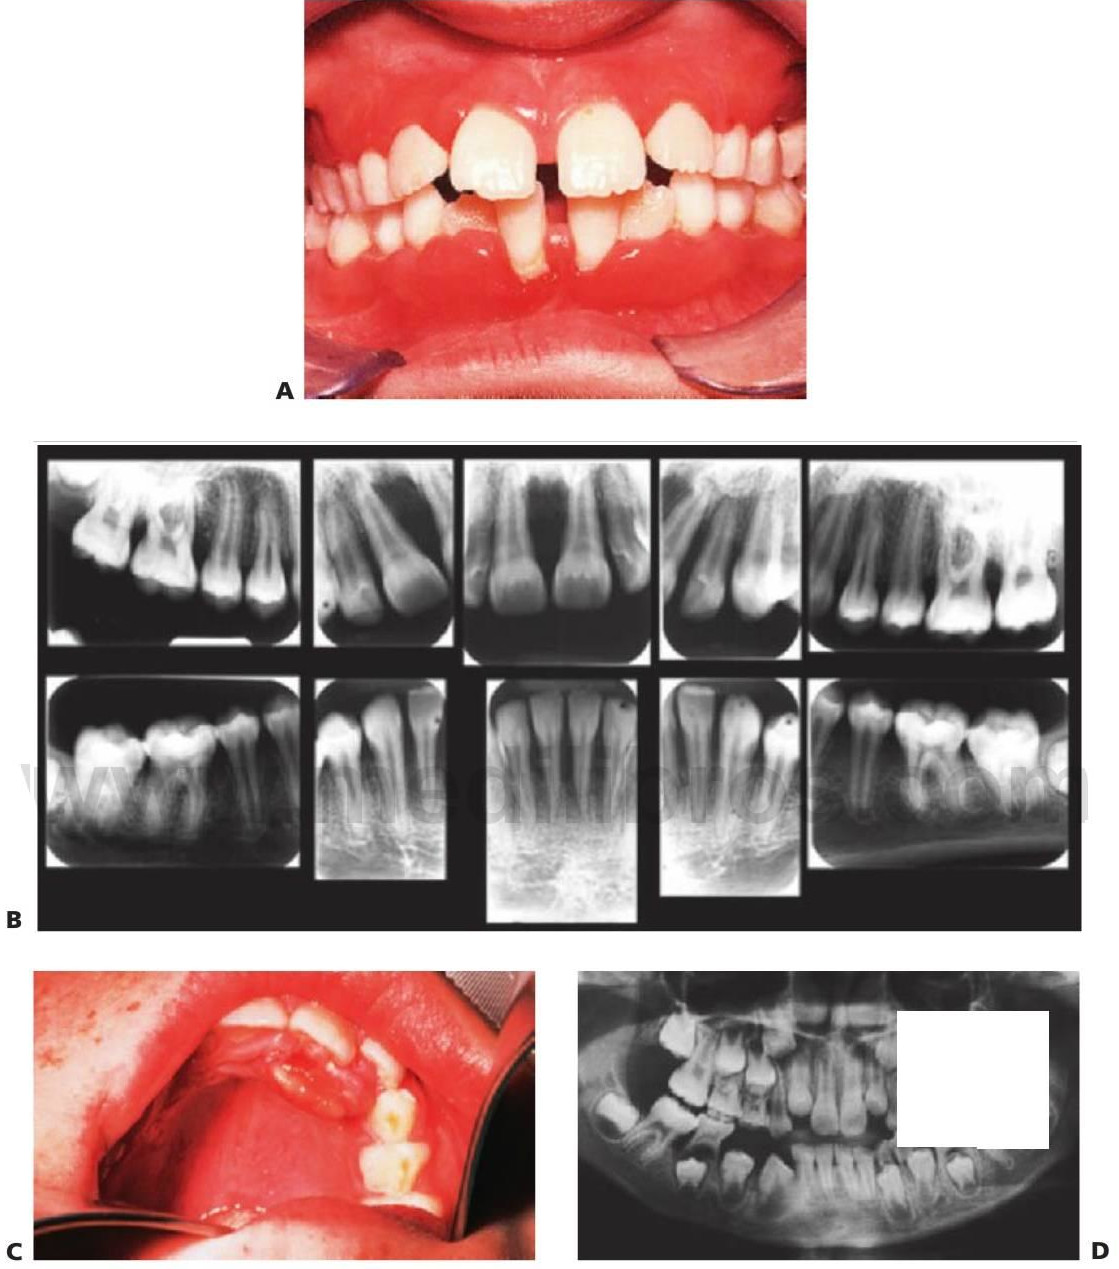

Enfermedad periodontal en niños

No es infrecuente la presencia de gingivitis en niños, pero la periodontitis con pérdida ósea alveolar suele ser la manifestación de un defecto inmunológico subyacente serio. Dos formas de enfermedad periodontal en niños, la periodontitis prepuberal y la periodontitis juvenil, se asocian a una flora bacteriana característica que incluye Actinobacillus actinomy-cetemcomitans, Prevotella intermedia, Eikenella corrodens y Capnocytophaga sputigena. Se cree que la presencia de estas bacterias está relacionada con una menor resistencia del huésped, sobre todo con la neutropenia o los defectos en la función de los neutrófilos. Los defectos en las células B muestran pocos cambios orales, pero la función alterada de las células T se manifestará con gingivitis, periodontitis y candidiasis graves (fig. 8.17D).

En este cuadro existe una disminución episódica del número de neutrófilos cada 3-4 semanas. Los recuentos de neutrófilos periféricos suelen bajar a cero y, durante este tiempo el niño es en extremo susceptible a las infecciones. Cuando el número de células es bajo, suele producirse una ulceración oral recurrente y los dientes sufren problemas gingivales y periodontales progresivos (fig. 8.17A, B).

Se trata de un trastorno autosómico recesivo caracterizado por una hiperqueratosis de las manos y los pies y por la exfoliación progresiva de todos los dientes debido a una enfermedad periodontal. La causa de tal enfermedad se atribuye a A. actinomycetemcomitans en asociación a un defecto cualitativo de los neutrófilos y mutaciones de las proteasas lisosomales del gencatepsina C en 11 q 14-21. Los dientes temporales empiezan a desprenderse en el momento de su erupción sin que se evidencie reabsorción radicular. Todos los dientes temporales suelen perderse antes de que erupcionen los dientes permanentes cuando ellos mismos se exfolian (fig. 8.18).

Este cuadro recibió en un principio el nombre de histiocitosis X, e incluía el granuloma eosinófilo, la enfermedad de Hand-Schüller-Christian y la enfermedad de Letterer-Siwe, y todas tienen en común la proliferación de células de Langerhans. Las lesiones orales se presentan de forma característica en los cuatro cuadrantes y afectan a los tejidos que recubren o dan soporte a los primeros molares temporales. Las lesiones se extienden normalmente hacia los caninos, pero no suelen afectar a los incisivos (fig. 8 19).

- Exposición prematura por reabsorción alveolar y pérdida subsiguiente de los dientes temporales, sobre todo los molares.

- En las radiografías, los dientes parecen estar «flotando en el aire».

El descenso en la fosfatasa alcalina sérica y el aumento en la excreción urinaria de fosfoenolamina (PEA) son patognomónicos de la hipofosfatasia. La forma más habitual se transmite con un patrón autosómico dominante, mientras que la forma autosómica recesiva es invariablemente letal. Se suelen perder, al menos, algunos de los incisivos antes de los 18 meses. Varios autores han identificado grupos de niños que manifiestan sólo cambios dentales y que presentan la pérdida precoz de dientes sin cambios óseos por raquitismo. Para estos pacientes se ha sugerido el denominado cuadro de odontohipofosfatasia, aunque se trata de un término inadecuado, ya que la pérdida de dientes por sí sola es sólo un extremo del espectro en la expresión variable de esta enfermedad. En estos niños se producen menos cambios graves, y hemos observado que la dentición permanente queda sin afectación (fig. 8.20).